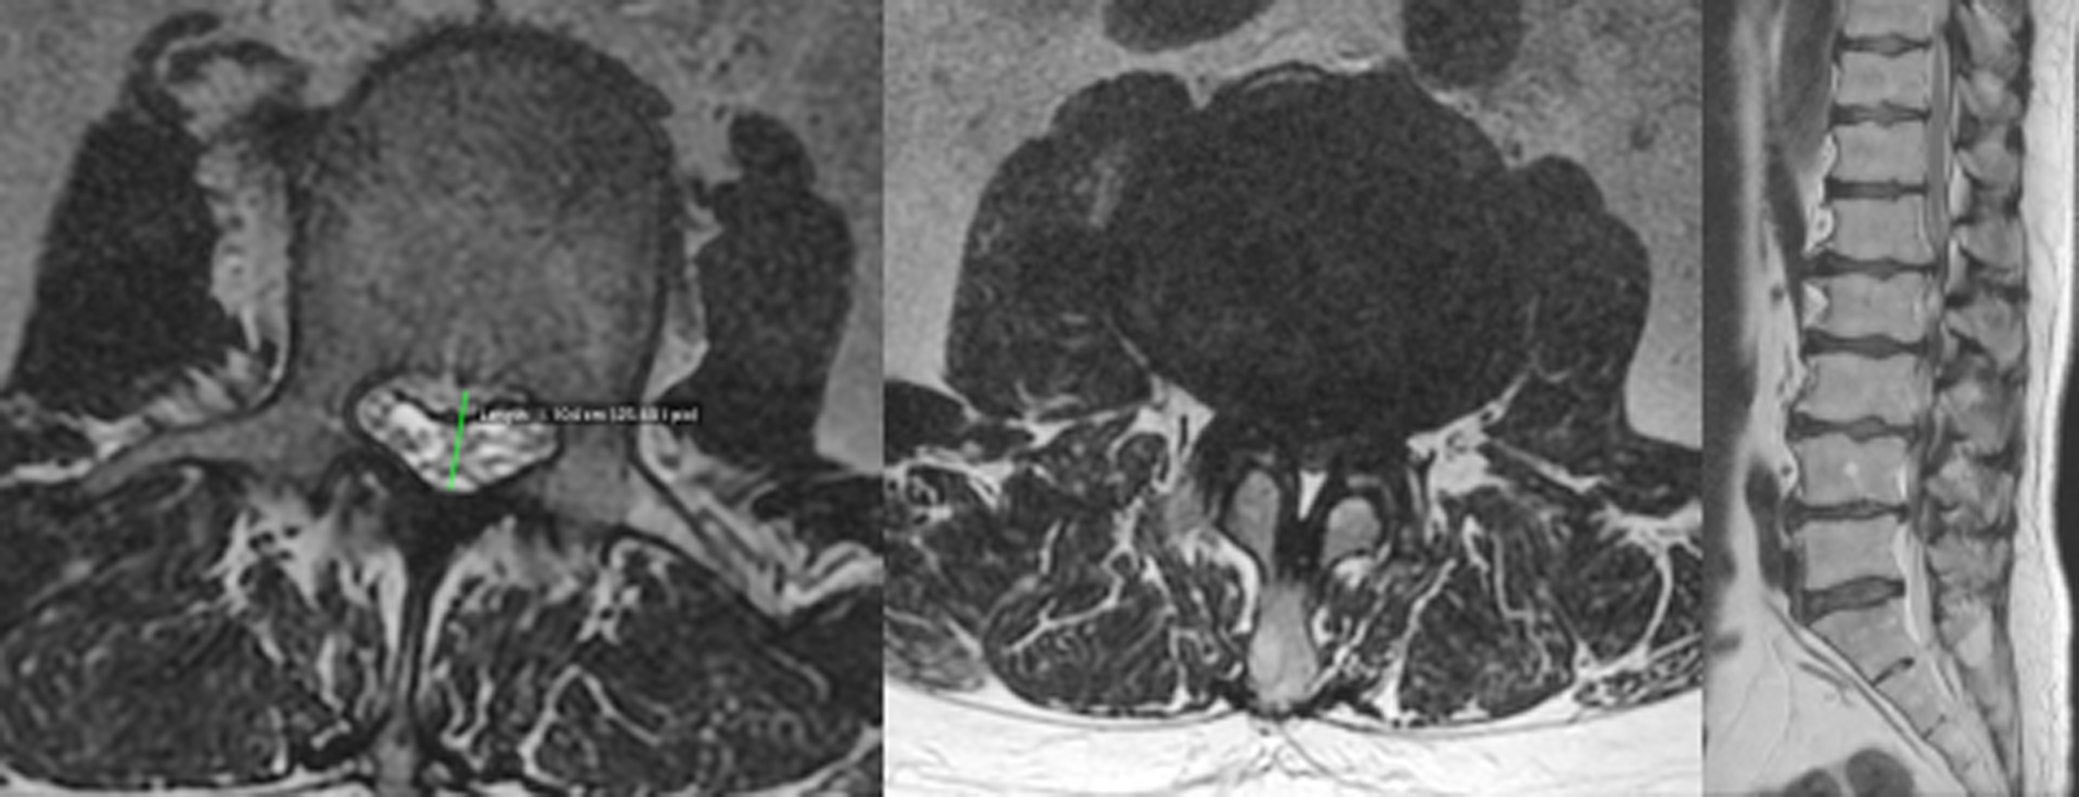

Ependymome myxopapillaire